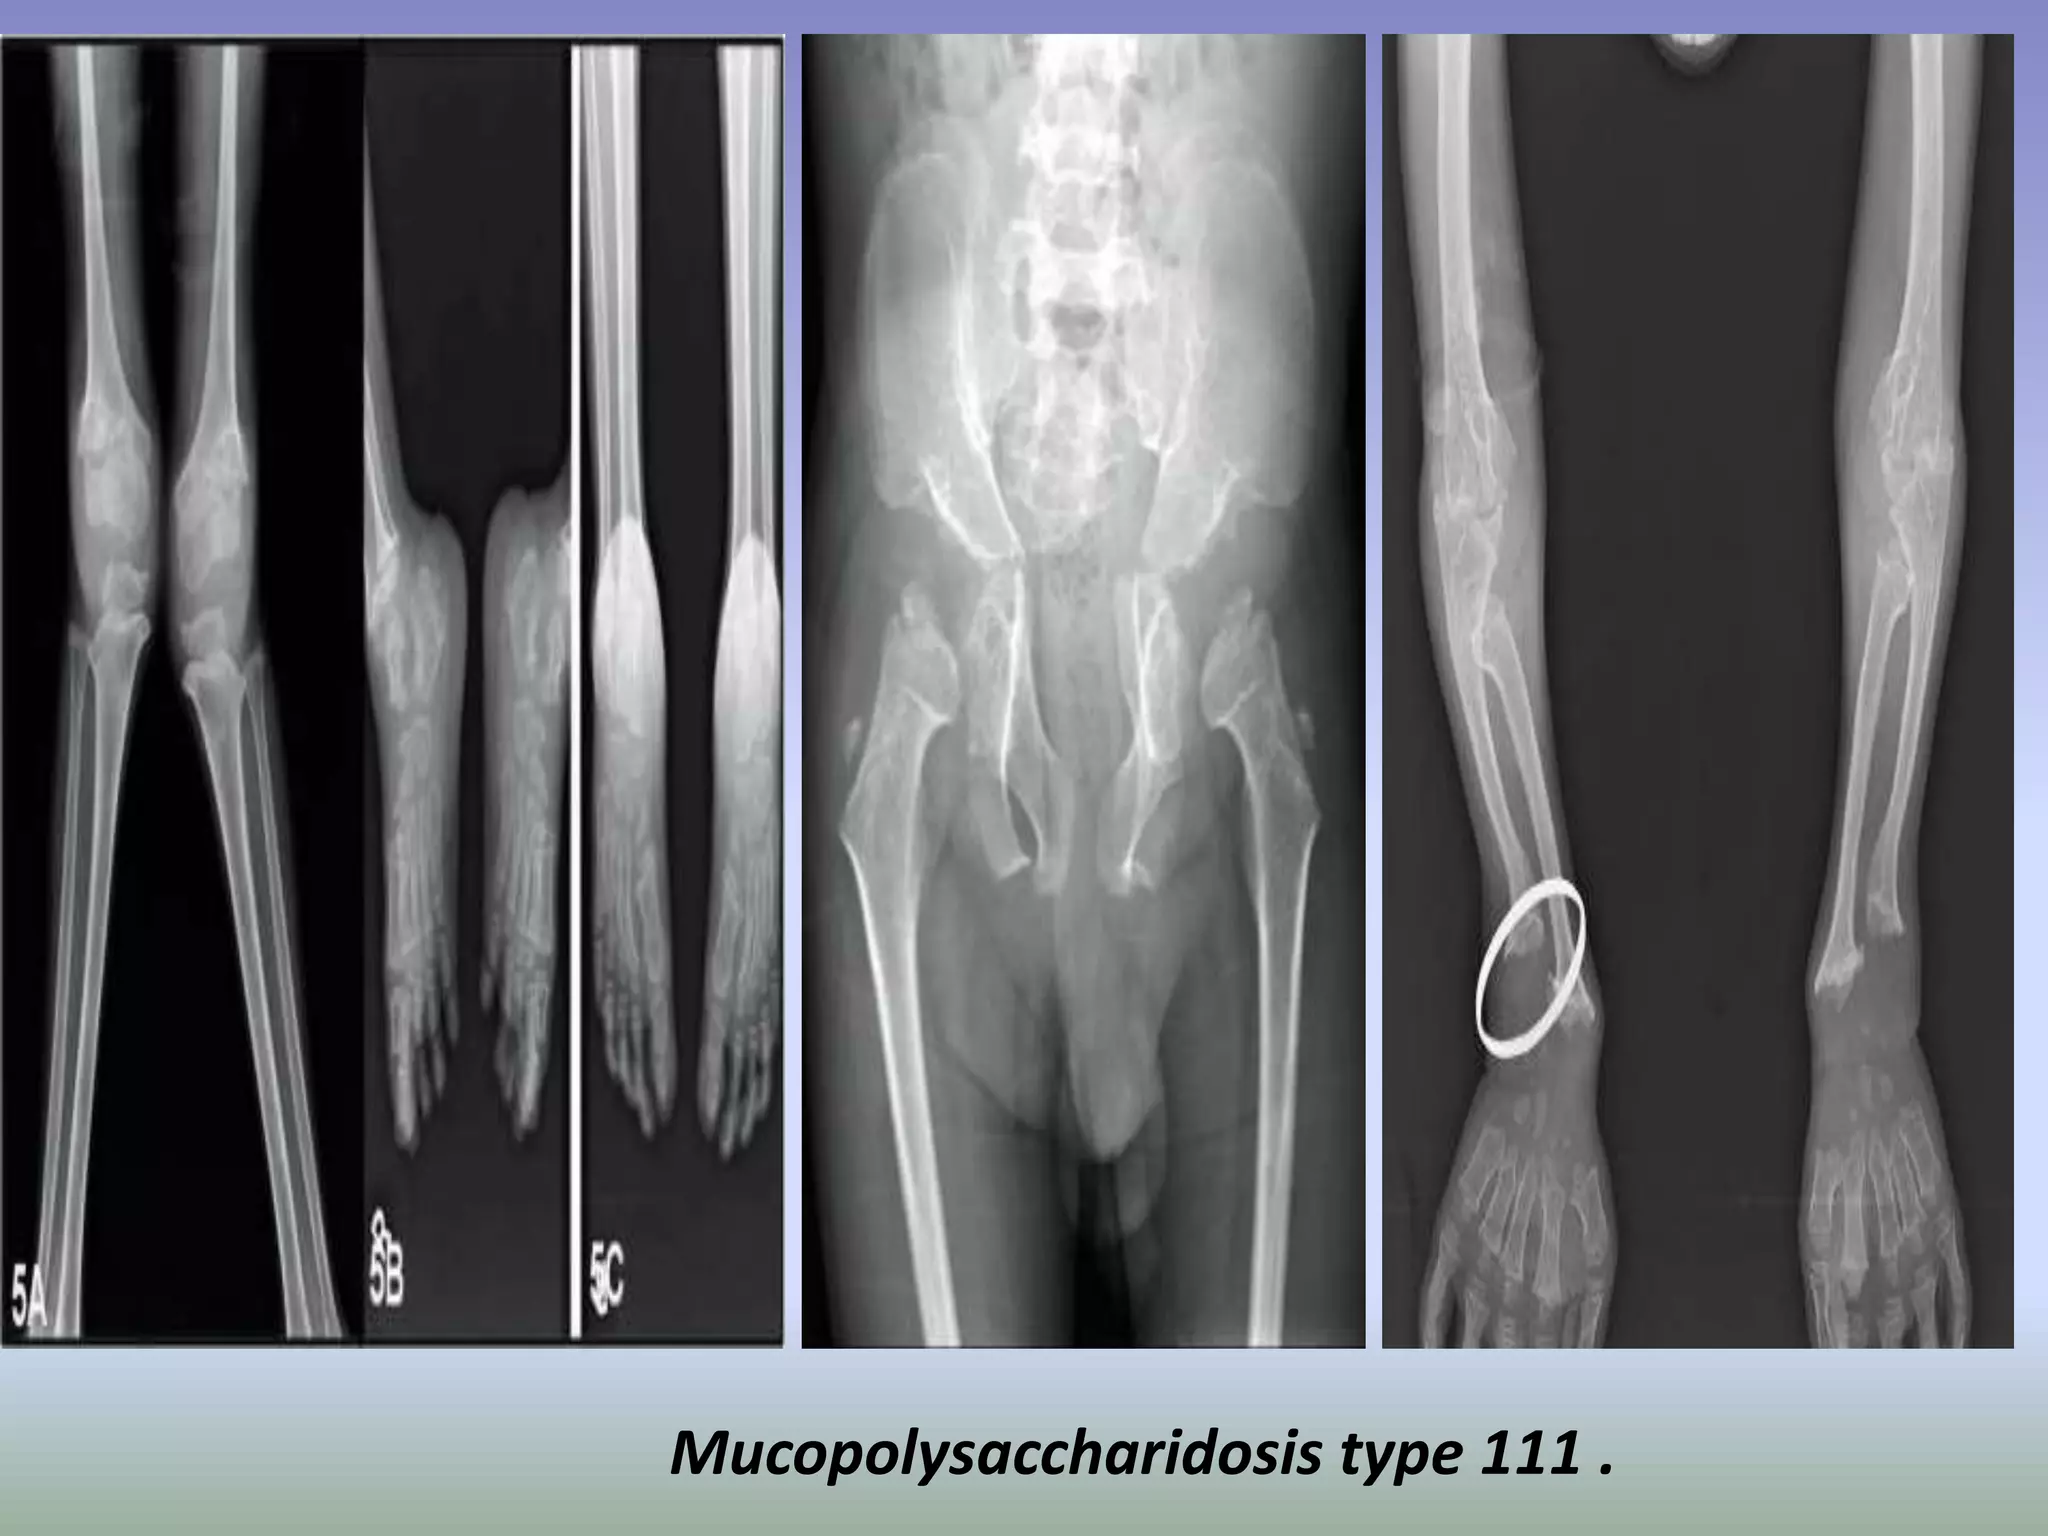

Mucopolysaccharidosis type 111 .